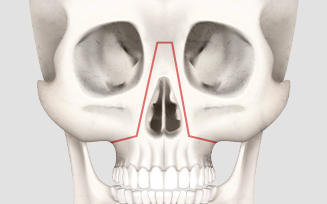

콧볼 정도의 위치에서

위턱 뼈를 절단하는 수술법으로

기본적인 상악 수술법

본원의 정필훈 이사장님

(서울대 치과대학 구강악안면외과 명예교수)이

직접 개발한, 코뼈를 포함하는 형태의

구강 내 상악 수술법

콧등, 콧대부터 콧망울까지 전체적으로 낮은

양악수술 대상 환자의 경우

서울페이스21만의 독자적인 디자인의 양악수술기법을 통하여

얼굴 피부의 절개나 흉터 없이 오직 구강내 절개만으로

낮은 코를 높일 수 있습니다.